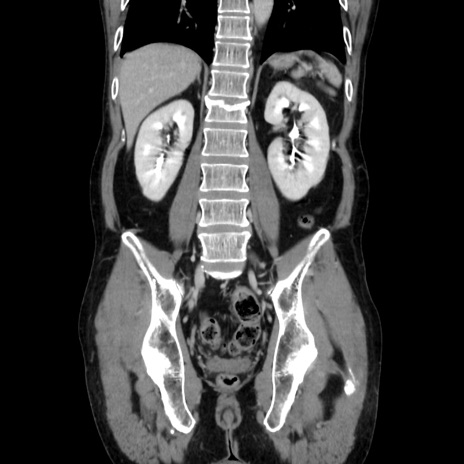

症例37(冠状断像)

【症例】40歳代 男性

【主訴】腹痛

【現病歴】4時間ほど前に電車に乗車中に臍部上より腹痛出現。徐々に増悪し起立困難となり、救急外来受診。生ものは数日食べていない。今朝お雑煮を食べた。

【身体所見】BT 36.8℃、BP 117/84mmHg、HR 91/min、SpO2 97%、苦悶様、腹部:臍上部広範囲圧痛あり、反跳痛±

【データ】WBC 8100、CRP 0.03

横断像